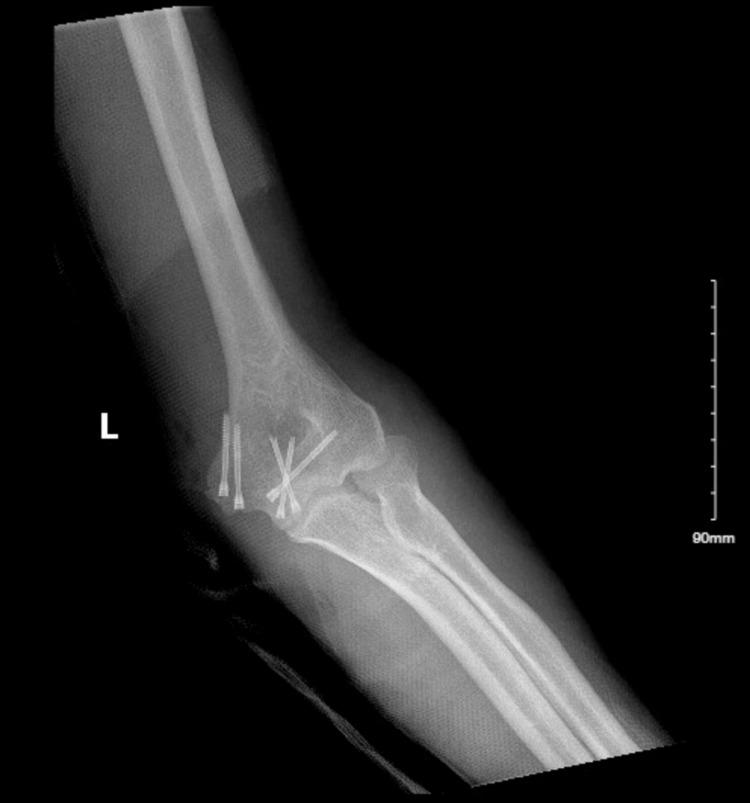

A Case of an Ulnar Nerve Laceration With Distal Humerus Fracture From Machete Trauma.

Ulnar nerve dysfunction following distal humerus fractures is a recognized phenomenon. There is no dominating consensus regarding the optimal management of the ulnar nerve during surgical intervention for these fractures between leaving the nerve in situ versus nerve transposition for better healing. Additional complexities arise in the case we present, in which there was an open fracture compounded with an ulnar nerve laceration from a traumatic injury with a machete knife. We review and discuss the management of ulnar nerve injuries associated with complex open fractures of the humerus for optimizing patient outcomes following these injuries.